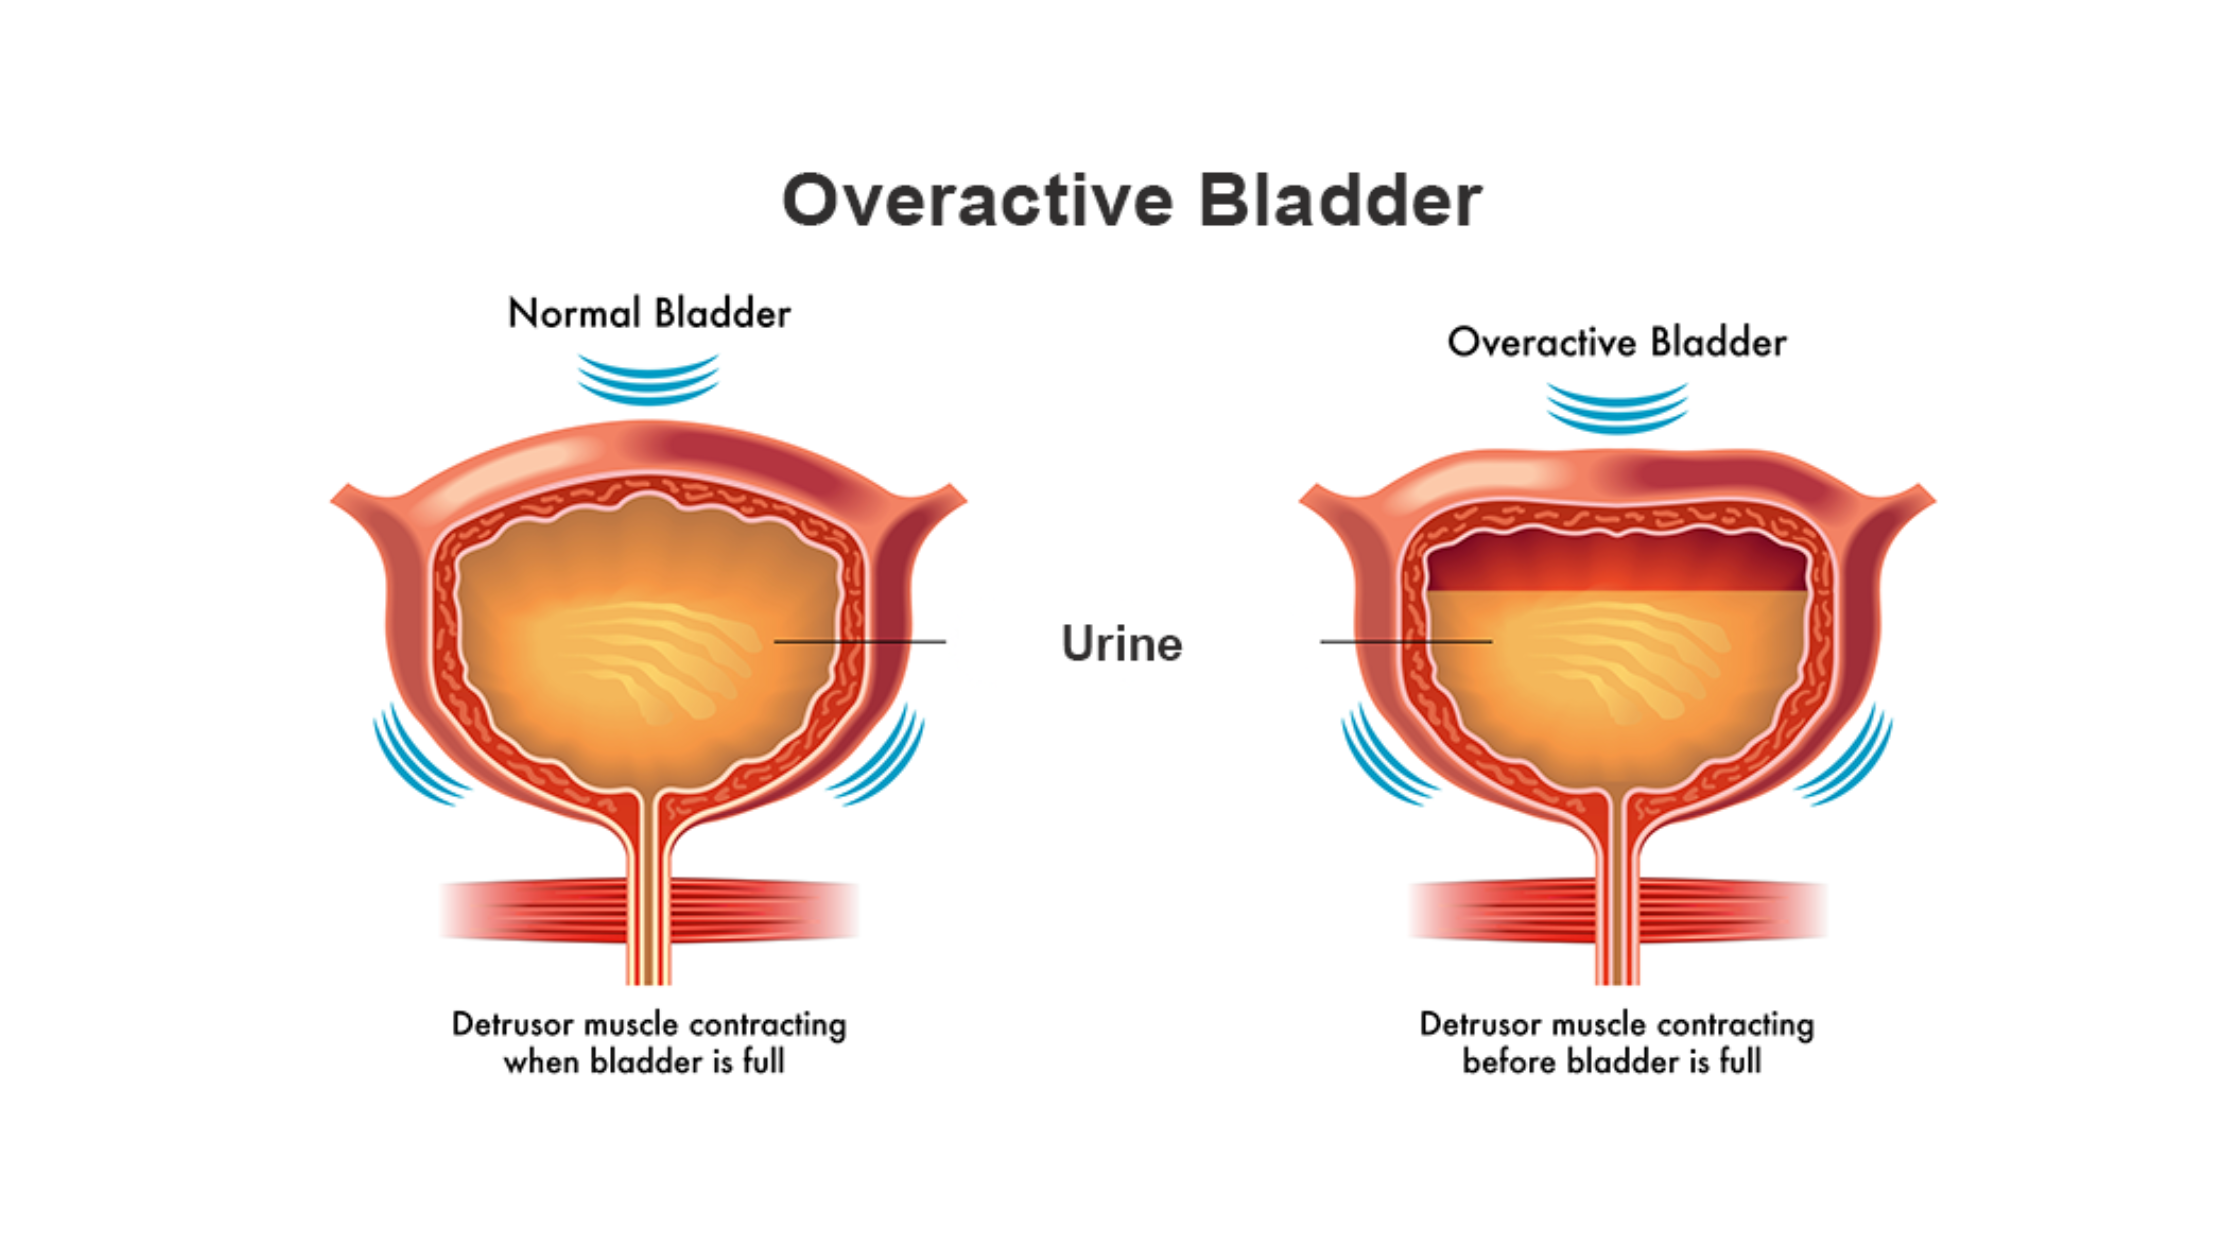

In the complex tapestry of human health, the often unspoken and misunderstood realm of bladder function plays a pivotal role. Overactive Bladder (OAB), a condition affecting millions globally, transcends mere […]